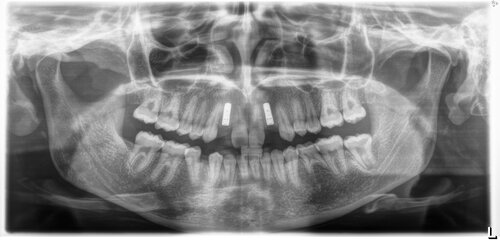

Before

The upper back molars were missing and the sinus was too low to proceed with dental implants. There was not enough bone present to place the implant.

Detailed view of oral anatomy captured via advanced imaging

After

We performed a sinus augmentation procedure to “lift” the sinus and place bone into the site so that a dental implants could be anchored properly, restoring molar function.